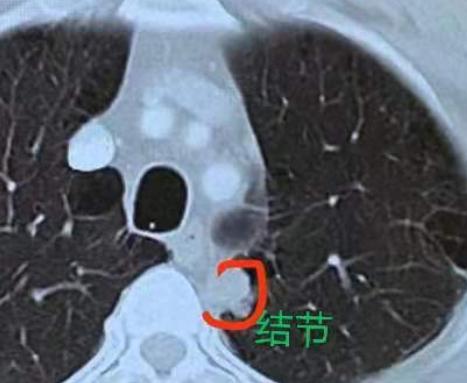

肺不好的朋友注意了!真实案例提醒:结节两年从无到长,别忽视体检!跟大家说个真实案

2026-01-29

乔贵

标签:

体检

肺结核

肺部肿瘤

慢阻肺